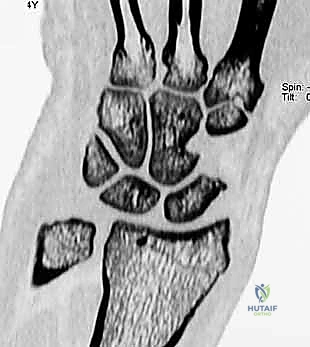

* CT Scans: Useful for precise measurement of static SLD parameters and ruling out osseous anomalies like impacted distal radius fractures or scaphoid fractures.

FIG 2 • B. CT scan of a patient with pain over the dorsal aspect of his left radiocarpal joint, showing a non-widened space between scaphoid and lunate, useful for baseline comparison.